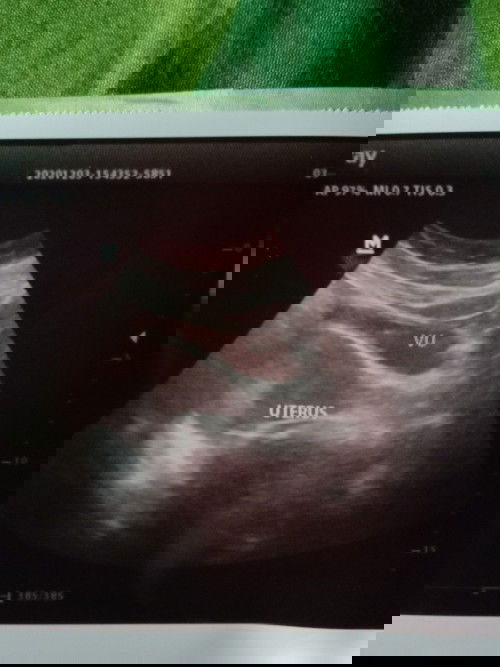

Mau nanya bun, aku hamil udh 10minggu tp aku ngalamin flek coklat pas aku usg kata dokternya usia kehamilan ku baru 5 minggu Besoknya keluar darah kaya mens trus setiap pipis keluar gumpalan darah 😭Aku harus gimana yaa?, udh kedokter cuman dikasih obat penguat smaa pemberenti darah tp pendarahnnya gak berenti2 juga 😭disini ada yg sama kaya akuu gakk ?? Trus akhir nya kaya apah ? Apah bisa dipertahankan ?#seriusnanya